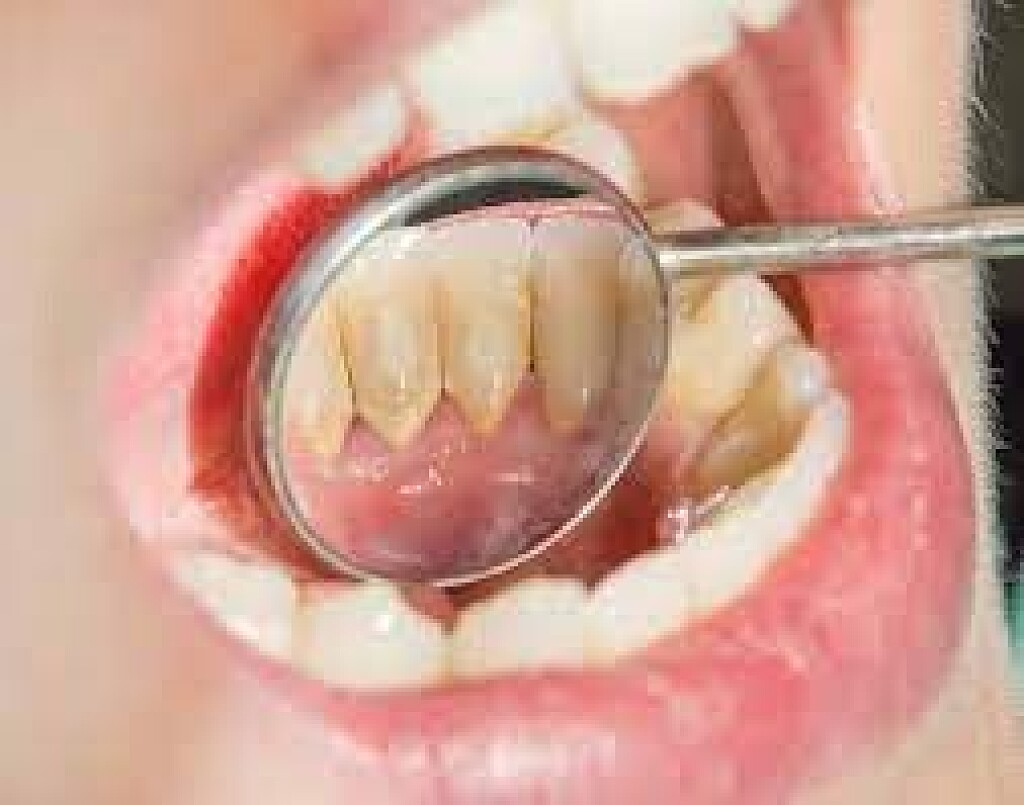

When plaque builds up in your mouth, it can turn into an even greater dental health threat: calculus. This formation, also known as tartar, is a calcified mass that adheres to your teeth. Calculus is classified as either supragingival or subgingival, depending on its location on your teeth. If left unremoved, subgingival calculus can lead to gum disease and tooth loss.

Tartar that accumulates on your teeth above the gumline and is easily seen by your dentist or dental hygienist is called supragingival calculus, according to the IJDHS article. But the tartar that forms below the gumline — and is therefore not immediately visible — is known as subgingival calculus. This type of calculus is usually dark brown to greenish black in color and can be detected with a dental instrument called an explorer.

It's important to note that, while you can clean plaque off your teeth with brushing and flossing, hard tartar can only be removed by a professional cleaning, explains the American Academy of Periodontology (AAP). Your dentist or dental hygienist uses special instruments that are designed to remove the calculus.

Calculus and Periodontal Disease

Calculus, including subgingival calculus, is associated with gingivitis, which is the first stage of gum disease, according to a review in the Journal of Health Sciences & Research (JOHSR). Typical early-stage gum disease symptoms include red, swollen gums and minor bleeding, according to the AAP. Luckily, the condition is often reversible with a good home care routine.

If left untreated, gingivitis can turn into periodontitis, where the plaque continues to spread beneath the gumline. When this happens, the AAP notes that the gum tissue eventually begins to pull away from the teeth, forming pockets that get infected. Pockets between the teeth and gums deeper than 4 millimeters may indicate that you have periodontitis, notes the Mayo Clinic.

When tartar builds up in the pocket, the bacteria can destroy the surrounding bone and tissue structures. Treatment of periodontitis usually involves scaling and root planing to remove all of the tartar, explains the Mayo Clinic. Periodontal surgery may also be necessary to treat any bone loss.

Preventing Calculus Formation